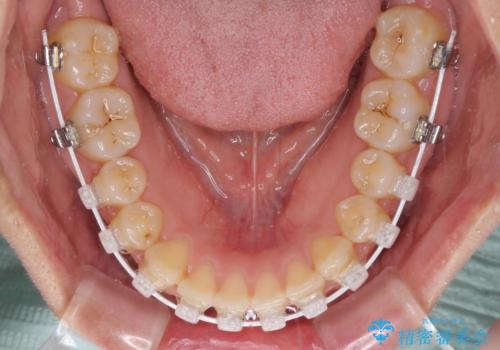

治療開始後すぐに妊娠され、つわりと闘いながらの矯正治療となりました。

上下顎でゴムかけを行ったのですが、早く終わらすためにしっかりと装着していただき、無事出産前に装置を外すことができました。